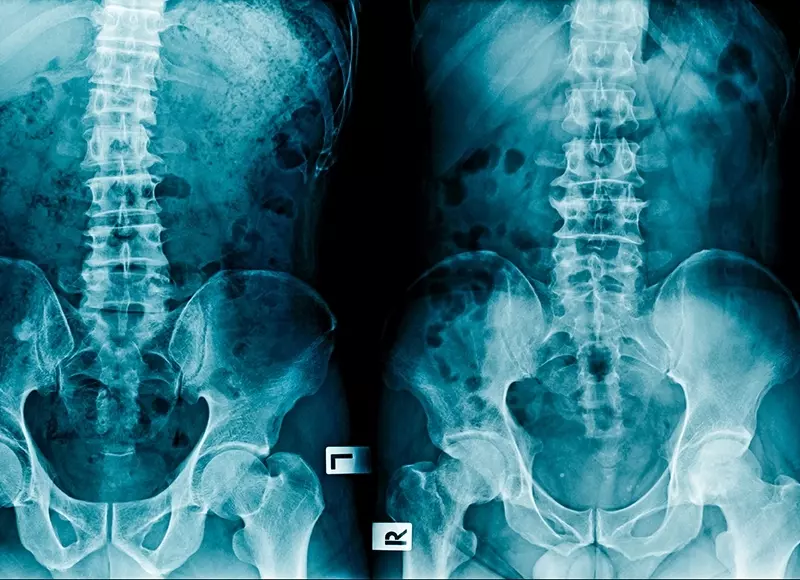

Również częstość pozaszkieletowych, okołoprotezowych skostnień po alloplastykach jest wysoka i może wynieść nawet 30% [16]. W materiale Kliniki WSZZ Kielce protezoplastyka w każdym przypadku była wtórnym zabiegiem do zespolenia (ryc. 1, ryc. 2) [17].

![]()

Ryc. 1. Radiogramy 68-letniej pacjentki operowanej z powodu wieloodłamowego złamania panewki prawego stawu biodrowego. Zabieg zespolenia panewki na 5 miesięcy przed endoprotezoplastyką. Zabieg endoprotezoplastyki metodą MIS DAA

A – złamanie wieloodłamowe panewki prawego stawu biodrowego, TK

B – stan po zespoleniu panewki prawego stawu biodrowego z dostępu K-L i biodrowo-pachwinowego (płyty miedniczne rekonstrukcyjne niskoprofilowe De Puy)

C – radiogram pooperacyjny po rekonstrukcji panewki (P. Pinnacle, T. Trilock De Puy) z dostępu MISS DAA

Ryc. 2. Radiogramy 59-letniej pacjentki operowanej z powodu złamania tylnej ściany z wyłamaniem powierzchni czworobocznej prawego stawu biodrowego. Zabieg z dostępu Kochera-Langebacka

A – radiogram przedoperacyjny przedstawiający złamanie tylnej ściany z wyłamaniem powierzchni czworobocznej

B – radiogram pooperacyjny przedstawiający zaopatrzenie ściany tylnej (dwie płyty miedniczne rekonstrukcyjne niskoprofilowe De Puy)

C – radiogram przedstawiający destabilizację złamania powierzchni czworobocznej panewki prawego stawu biodrowego na skutek upadku

D – radiogram pooperacyjny po rekonstrukcji panewki (P. Pinnacle, T. Trilock De Puy) z dostępu Kochera-Langebacka

E – radiogram wykonany po 24 miesiącach po zabiegu endoprotezoplastyki, przedstawiający destabilizację panewki